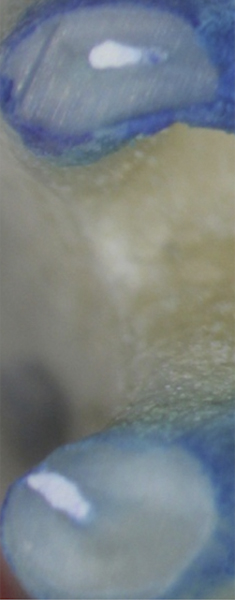

Figure 7. Preoperative pulp exposure after caries removal. Courtesy of Dr. Mohammed A. Alharbi.

Figure 7

Figure 8. Direct pulp coverage with BC Putty. Courtesy of Dr. Mohammed A. Alharbi.

Figure 8

Case 1: Direct Pulp Cap

Figure 6 shows the preoperative radiograph of an apparent carious exposure on tooth No. 19 of a 20-year-old male patient. A diagnosis of reversible pulpitis was made based on the history and clinical exam. After anesthesia and caries removal, the exposure was seen (Figure 7) and covered with BC RRM-Fast Set (Figure 8). After the BC base had fully set, a bonded resin was placed and a postoperative radiograph taken (Figure 9). At the 6-month follow-up visit, the tooth was asymptomatic and tested vital. Radiographically, no signs of pathology were noted (Figure 10).